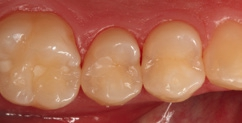

Fall 8 Multiple Läsionen an Zähnen 26 und 25

Bei dem 37-jährigen Patienten imponierte eine Approximalraumkaries mesial an Zahn 26 und distal an Zahn 25. Zudem waren okklusal und okklusal-palatinal (getrennt durch den Transversalgrad) zwei kleinere, randundichte ältere Amalgamfüllungen vorhanden, die ausgetauscht werden sollten. Der Patient hatte zunächst die Empfehlung einer Teilkronenversorgung erhalten; aufgrund der Situation nach der Exkavation und der noch sehr umfangreich vorhandenen Restzahnhartsubstanz erschien eine direkte, minimalinvasive Versorgung mit Komposit angebrachter. Die Abbildung 35 zeigt die bereits präparierten und mit Teilmatrizen (Contact Matrix Ultra thin flex, Danville, Spannring: Palodent V3, Dentsply Sirona) versehenen Kavitäten, die Abbildung 36 die Situation nach der adhäsiven Versiegelung mit einem klassischen Mehrflaschenadhäsiv (Optibond FL, Kerr). Auch hier war aufgrund der guten Compliance und der suffizienten zervikalen Abdichtung über die Matrize ein Arbeiten unter relativer Trockenlegung sehr gut möglich. Die Abbildung 37 zeigt das Behandlungsergebnis bei einem Kontrolltermin nach zwei Wochen. Die beiden approximalen Kavitäten wurden ausschließlich mit SDR flow+ in der Farbe A2 versorgt, die okklusal-palatinale und die separate okklusale Kavität hingegen mit einem konventionellem Komposit (ceram.x universal, Dentsply Sirona). Die Wahl fiel hier auf das pastöse Material, da mit diesem die Ausmodellation der Fissur einfacher gestaltet werden konnte. Die in der Abbildung erkennbare, approximal nicht kavitierte Initialläsion distal an Zahn 24 wird durch regelmäßige Intensivfluoridierung über eine Remineralisation therapiert und halbjährig gemonitort.